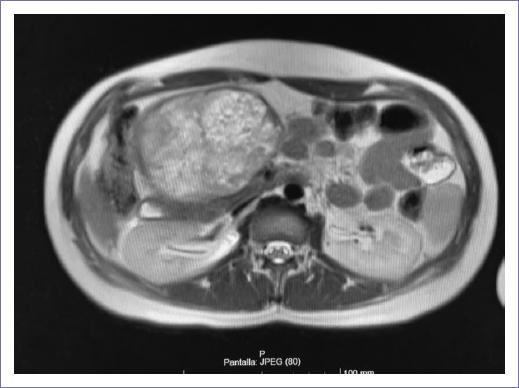

Paciente de sexo femenino de 18 años, de ocupación estudiante de bachillerato, sin antecedentes personales patológicos, no patológicos y familiares de relevancia, acudió a urgencias por un aumento de masa en la región superior del abdomen de 11 meses de evolución con un crecimiento lento y progresivo, dolor abdominal, acompañado de vómito y plenitud posprandial. Se envió a la consulta de cirugía oncológica de forma urgente, en donde a la exploración se palpó una masa en hipocondrio derecho, pétrea, sin límites definidos, sin datos de ascitis. En los estudios de gabinete no hubo elevación de marcadores tumorales y en la tomografía computarizada (TC) de abdomen trifásica (Fig. 1) se reportó un tumor en la cabeza y cuerpo de páncreas heterogéneo de 10 x 10 x 8 cm que desplazó la vena porta, con pérdida de la interfase en la placa portomesentérica de 180 grados.

Figura 1 Tomografía computarizada de abdomen trifásica. Tumor de cabeza de páncreas heterogéneo, de 10 x 10 x 8 cm que desplaza vena porta, pérdida de la interfase en la placa portomesentérica 180 grados.